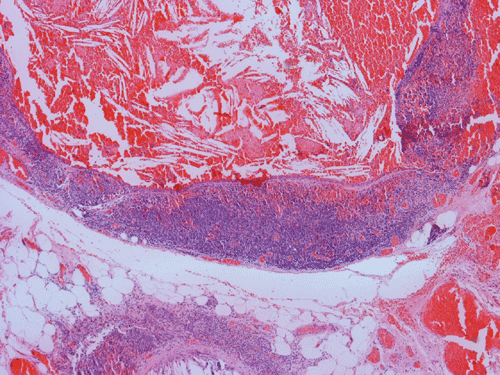

Clinical information: The patient is a 36 year-old woman who presented with a 2 cm swelling in the left side of her neck. The mass was not tender, warm, or painful. The overlying skin was unremarkable. A CT scan was performed and showed a 1.8 x 1.2 cm relatively non-enhancing lesion within the carotid sheath displacing the carotid artery anterioriorly. The clinical and imaging features yielded an empirical diagnosis of an enlarged lymph node. The patient had no history of lymphoma, leukemia, or head and neck tumor. The mass was removed surgically in its entirety and was 2.5 cm in maximum dimension, well encapsulated, located at the level of the carotid bifurcation just lateral to the carotid artery and superiorly extending almost up to the level of the tonsils. The mass did not appear to be in continuity with the jugular vein or the carotid artery. It was not a part of the vagus nerve or sympathetic chain. The followings are representative images.